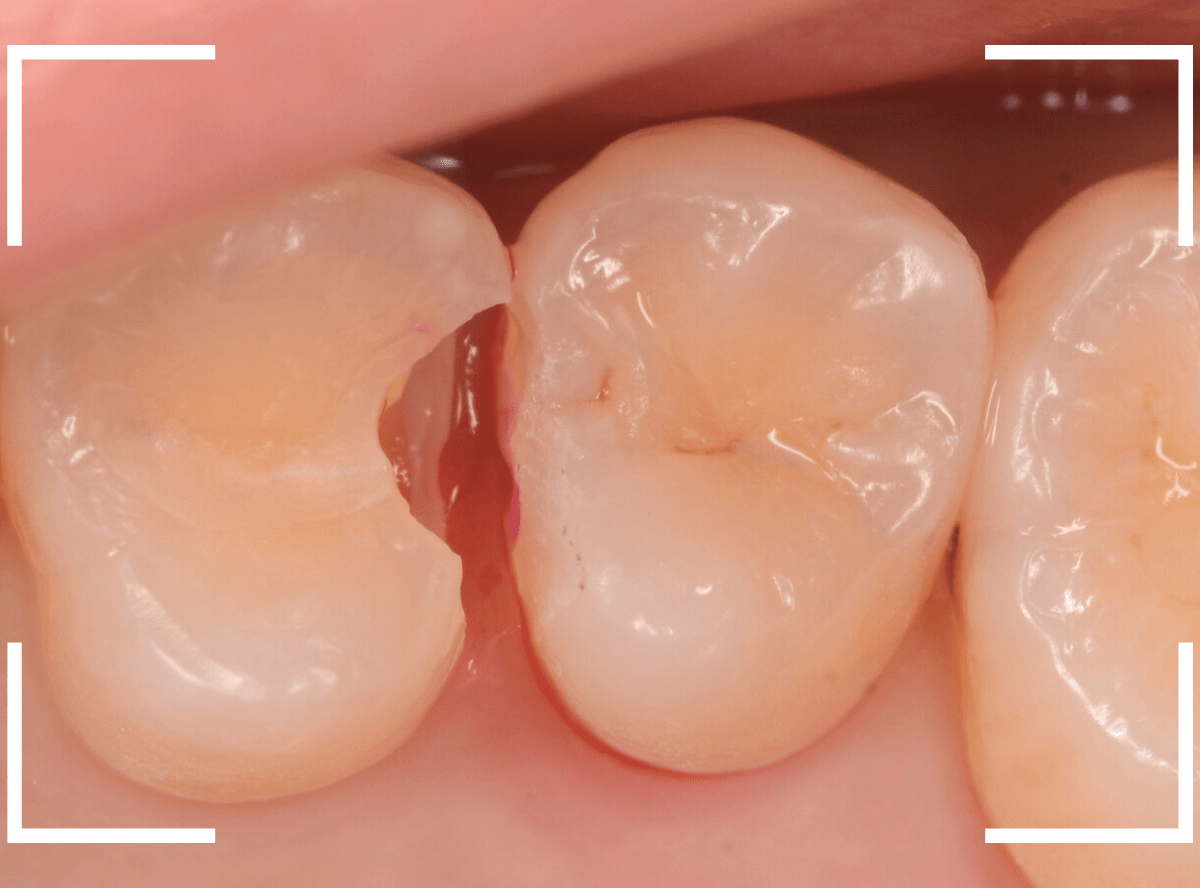

Case.9 レントゲン写真で写らない側面の虫歯

歯の側面が大きな虫歯になってしまった患者さんのケースです。

このように歯の側面が虫歯になった場合、レントゲン写真で虫歯の状況がはっきりわからない事が多いです。

レントゲン写真では、あまり大きな虫歯のようには見えません。

治療を開始します。

歯を少し削ると、すぐに大きな虫歯の穴が出てきました。

さらに虫歯を削ります。

神経に触れてしまいそうなほど、深くて広い虫歯ですね。

全ての虫歯を除去したところです。

何とか神経に触れる寸前のところで踏みとどまれましたが、レントゲン写真からは想像できない虫歯の深さでした。